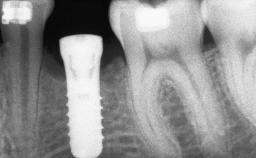

A 47-year-old woman who had suffered from aggressive periodontitis requiring a number of periodontal interventions over more than 10 years was referred by her general dental practitioner and periodontologist for bone augmentation and implant therapy. Her failing dentition had already been scheduled for extraction. The patient expressed a desire for implant-supported fixed restorations and esthetic improvement of her lower face. She had agreed to consult with a maxillofacial surgeon after the referring dentist had suggested bone augmentation. An initial examination by the maxillofacial surgeon revealed mobility of all residual teeth in a patient who was very unhappy with the function of her removable partial dentures. Due to periodontally migrated flaring teeth and loss of occlusal support, the vertical dimension of occlusion was dramatically reduced. The patient was displeased with her lower face because of deepened nasolabial, commissural, and supramental folds.

# of Implants 14

Bone Volume Deficient vertically or deficient vertically AND horizontally